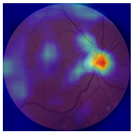

| No. | Fundus Image | Grad-CAM | Group | PRS | CNN | CNN+ML |

|---|---|---|---|---|---|---|

| 1 |  |  | Control | −1.07 | −0.57 | −1.95 |

| 2 |  |  | Control | −0.30 | −0.85 | −1.50 |

| 3 |  |  | Control | −3.12 | −1.53 | −1.83 |

| 4 |  |  | AMD | −0.99 | 0.29 | −0.86 |

| 5 |  |  | AMD | −0.23 | −0.29 | −0.66 |

| 6 |  |  | AMD | 0.17 | 1.31 | −0.75 |

| 7 |  |  | AMD | −0.43 | 1.16 | −0.48 |